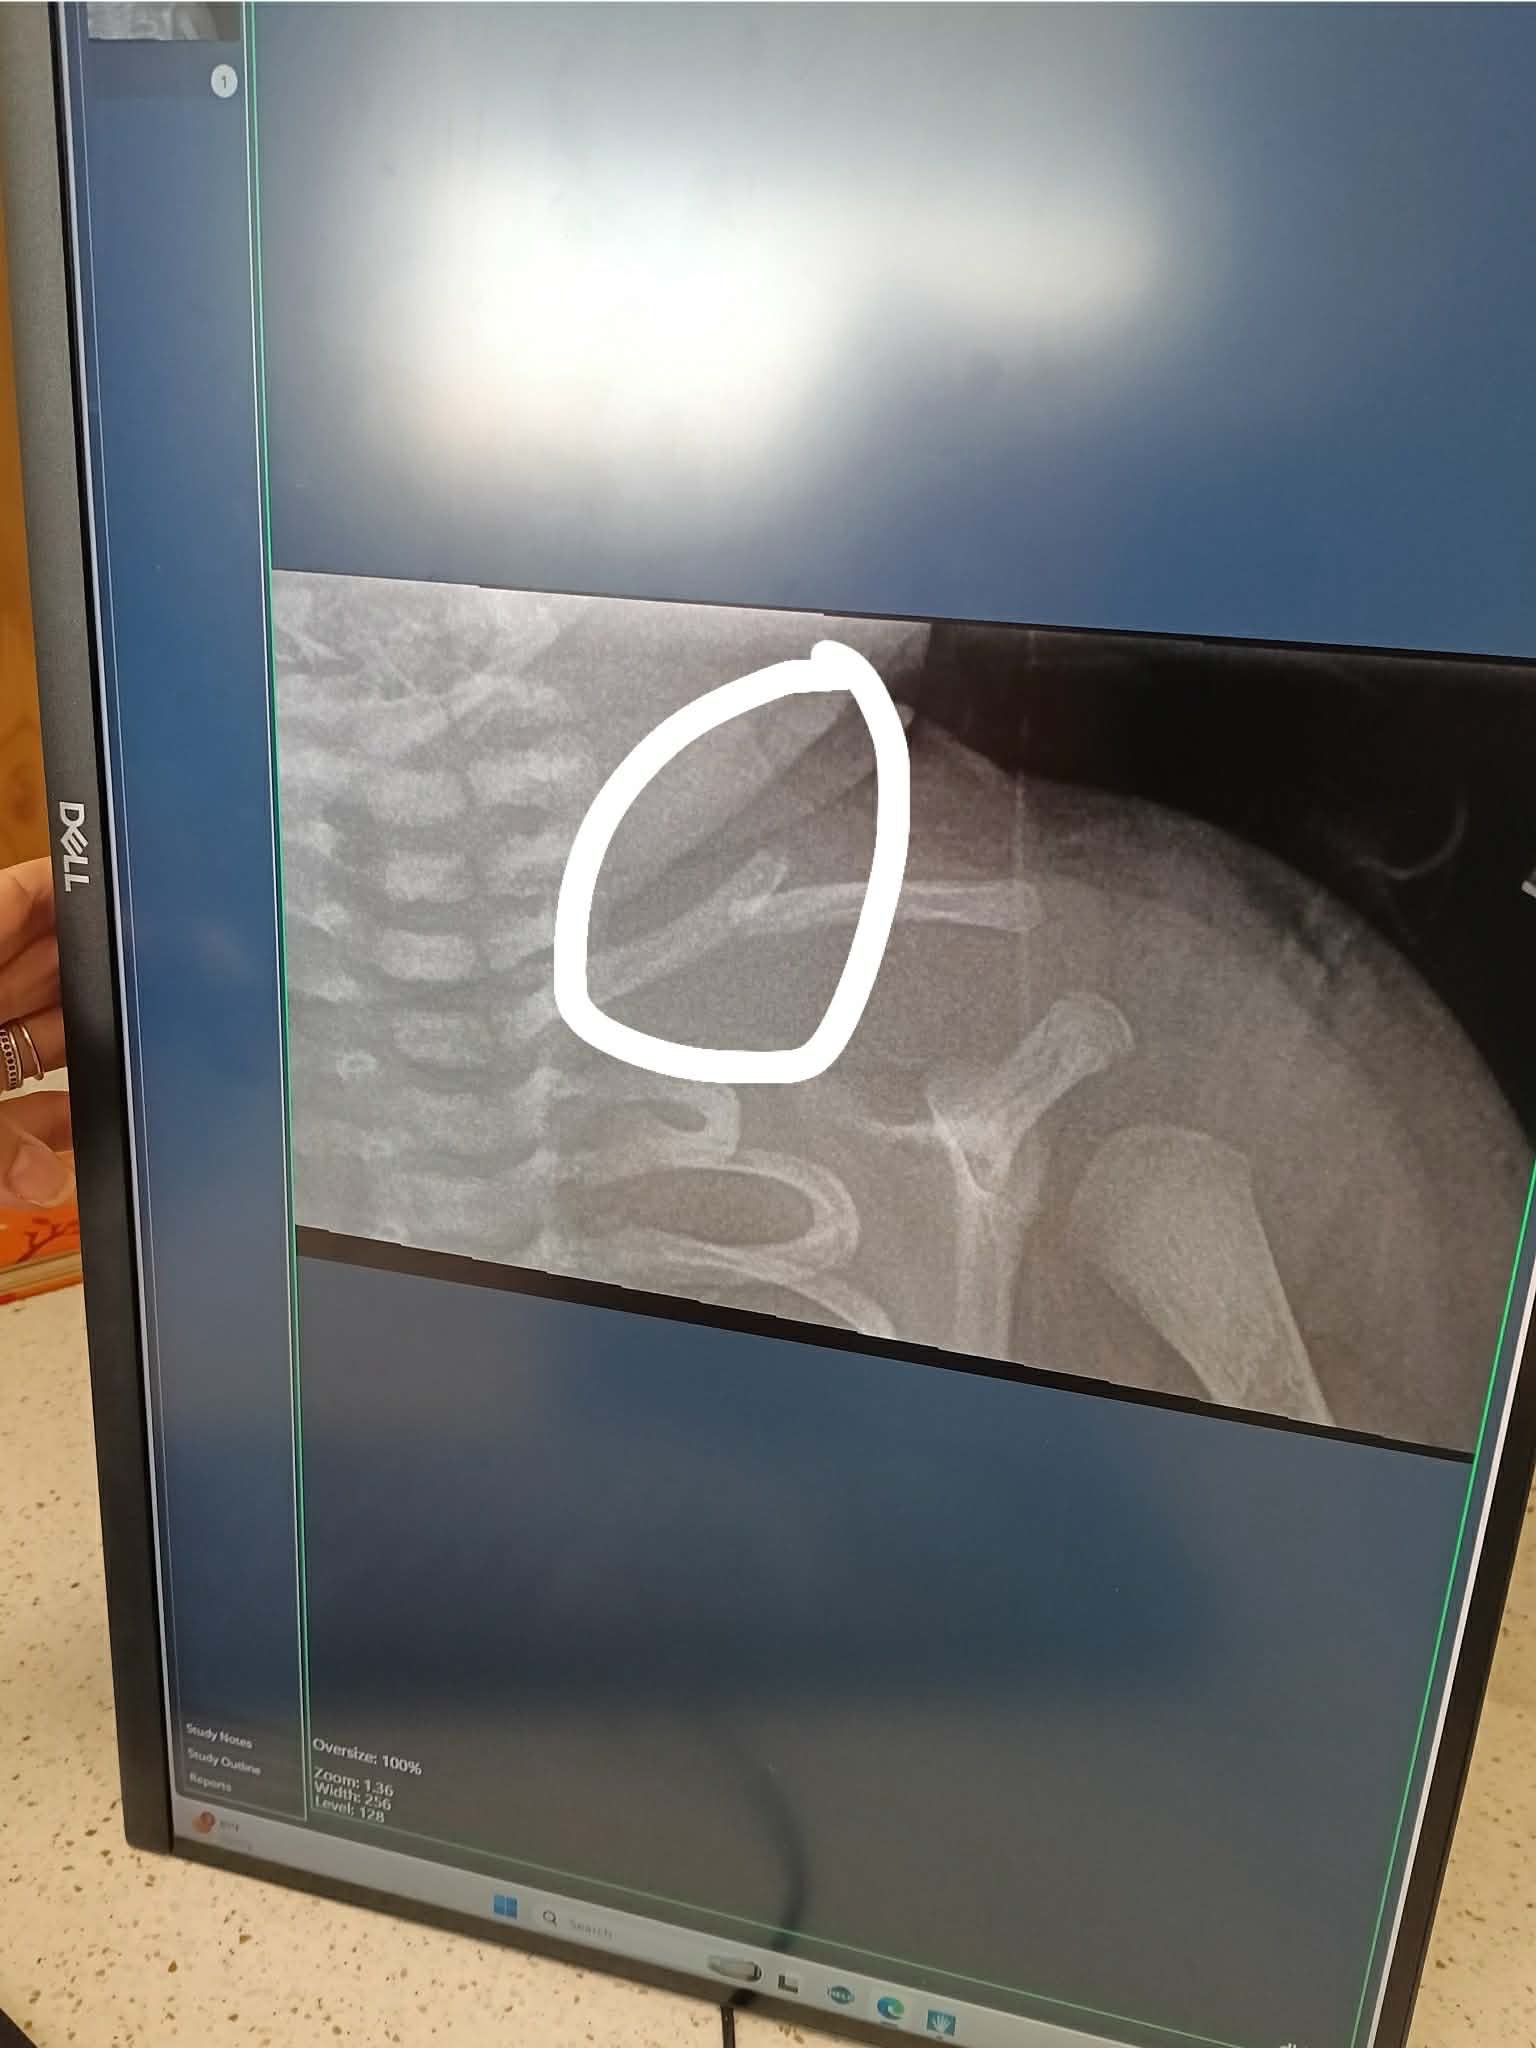

On March 26, 2026, I welcomed our precious daughter, Jeanlle'Grace, into the world. Our joy quickly turned to worry when we learned she had suffered a birth injury—a broken left collarbone—and was diagnosed with cerebral palsy affecting her left arm. Since then, our days have been filled with doctor visits, sleepless nights, and prayers for her healing. Insurance only covers a limited number of X-rays, but Jeanlle'Grace needs two or more X-rays every month to make sure her collarbone is healing properly. Each set of X-rays is an out-of-pocket expense, which is a heavy burden for our family since I am not working and my husband is the sole provider. Even with the sleepless nights my heart breaks for our sweet girl. Specialist say it will take over a year to heal. Appointments after appointments: From one X-Ray to another (a lot of radiation through such a tiny body), neurology checks, blood work, occupational therapy, and physical therapy.